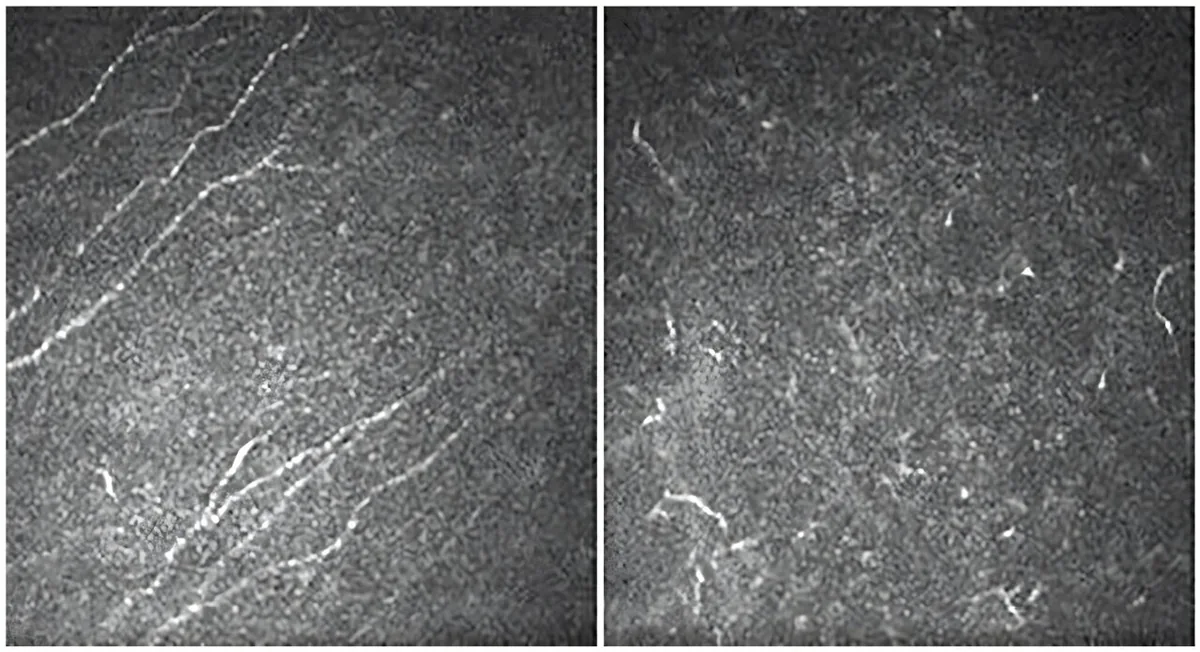

Clinical Study: Aniridia Triggers Progressive Corneal Sensitivity Loss

Congenital aniridia represents a uncommon medical condition primarily triggered by genetic mutations in the PAX6 gene, a critical factor in the proper formation of various eye structures. While the condition is most noticeably characterized by the complete or partial lack of the iris, its impact extends well beyond this apparent trait. Individuals living with aniridia […]